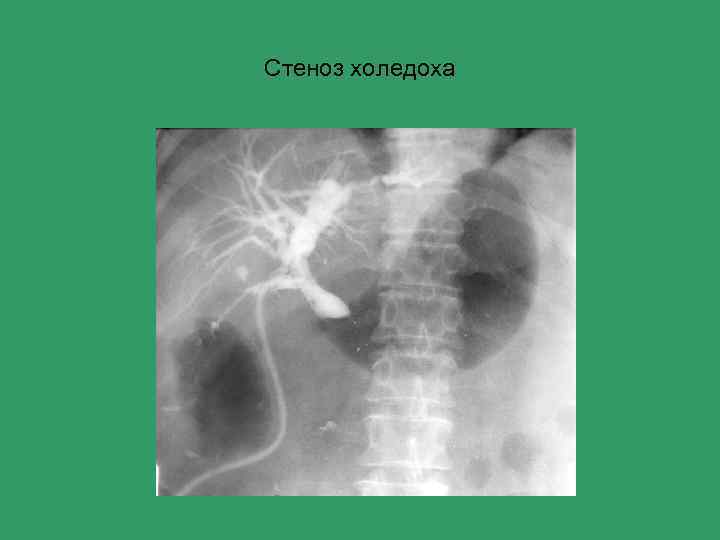

Стеноз холедоха